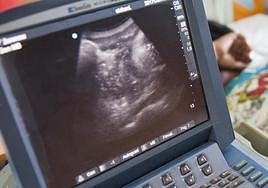

El presidente incide además en la necesidad de abrir «una nueva etapa de descentralización» e inscribir «lo antes posible» el derecho al aborto en la Carta Magna